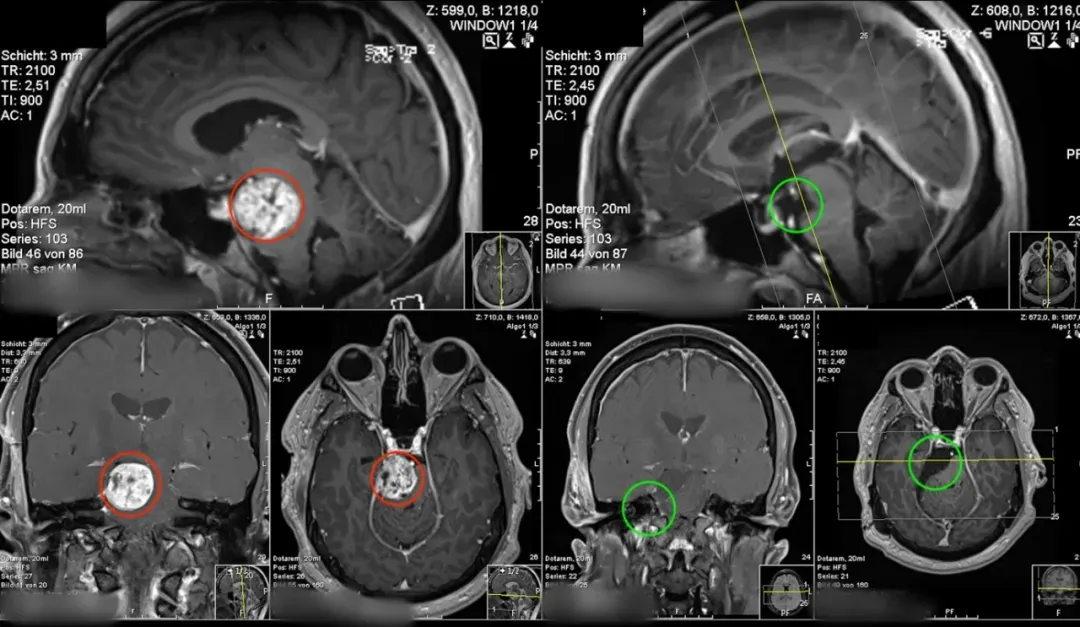

MRI图像显示神经鞘瘤的典型结构,直径约3cm,与右腱膜和Meckel区域有着广泛的关系,并显著压缩和移位脑干,尤其是上部脑桥和下部中脑区域。

肿瘤延伸到背侧蝶鞍和右后斜突,位于移位的动眼神经前方。脑后动脉和小脑上动脉也受到肿瘤的影响并改变了正常位置。

(术前术后MR对比)